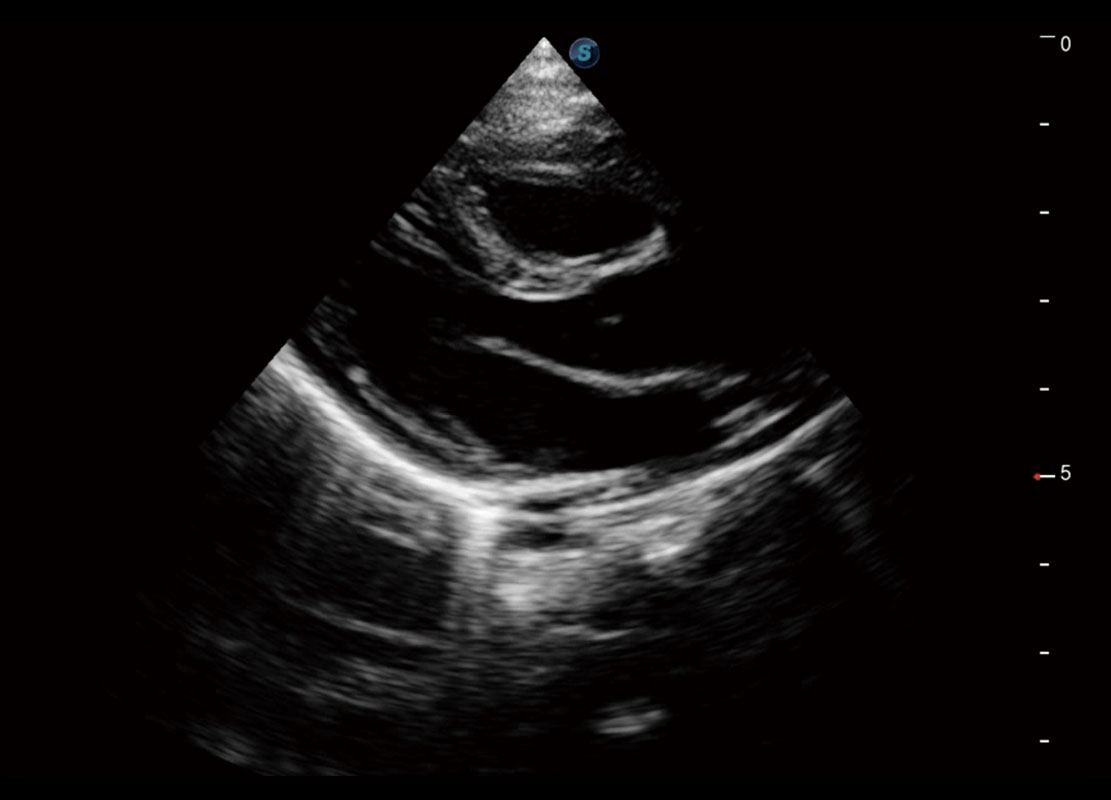

• 四腔切面

• 四腔心血流